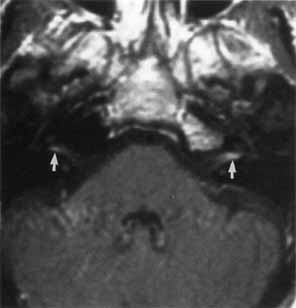

| A wide variety of spontaneous, anomalous facial movements occur with surprising

Although the underlying pathophysiology of this disorder is unknown, the concept of ephaptic transmission remains a dominant theory.132–134 Ephaptic transmission refers to a lateral spreading of neural impulses by damaged axons that excite adjacent nerve fibers. This leads to the spontaneous and simultaneous contraction of adjacent facial muscles. Anomalous facial motor nucleus firing is an alternative theory. Ferguson135 has suggested that damage to the facial nerve near its root entry zone, or in the brain stem, leads to deafferentation of the facial motor nucleus. This would result in augmented and automatic firing of the facial motor nucleus, presumably by disinhibition and reorganization of the central nuclear pool. Other cases are recorded after idiopathic palsy and with extramedullary compression by tumor.136 Neuroradiologic imaging, especially MRI of the posterior fossa, should be performed to exclude compression of the facial nerve by tumor (Fig. 24). magnetic resonance tomographic angiography is currently the most sensitive test to detect vascular compression of the seventh nerve at its exit zone.131,137 Neurosurgical treatment is directed toward decompression of the facial trunk at its exit from the brain stem in proximity to a tortuous or dolichoectatic anteroinferior cerebellar, posteroinferior cerebellar, vertebral, or basilar artery (see Fig. 24).10 The surgical approach is by way of a suboccipital craniotomy with placement of a sponge prosthesis between the facial nerve and the offending artery. In a series of 54 patients, Auger and colleagues138 reported complete relief in 70% of patients who underwent microvascular decompression for hemifacial spasm; 11% had initial improvement followed by a recurrence of facial spasm within 2 years, whereas another 9% had improvement without total resolution. Only 9% of patients showed no benefit. The mean follow-up period was 3.9 years. Complications included unilateral hearing loss, transient and permanent facial weakness, facial numbness, and unsteady gait. In a series of 310 patients treated by microvascular decompression of the facial nerve, over 90% had complete relief of spasm with a late recurrence of only 1%.139 Other surgical approaches include unilateral myectomy 140 and facial neurotomy.124 Medical therapy with carbamazepine141 and baclofen142 has also been successful in relieving hemifacial spasm in some patients. Injection of botulinum A toxin into the orbicularis oculi muscle has become standard treatment of hemifacial spasm.128 FACIAL SYNKINESIS When a patient suffers a seventh nerve paresis, he or she may subsequently demonstrate ipsilateral involuntary narrowing of the palpebral fissure upon volitional contraction of the orbicularis oris (Fig. 25) and other facial muscles (i.e., during pursing the lips, forceful opening of the mouth, smiling, or chewing with the mouth closed). In addition, lower facial muscles may contract during volitional eye closure. This phenomenon is due to aberrant regeneration of the seventh nerve with sprouting of axons to supply more than one muscle group. Frueh143 used electromyography to show that the narrowing of the palpebral fissure was secondary to contraction of the ipsilateral orbicularis oculi muscles and not due to inhibition of the levator superioris. At present, there is no effective way to prevent intrafacial synkinetic phenomena. Injections of botulinum toxin into the orbicularis oculi muscle may provide temporary relief.128